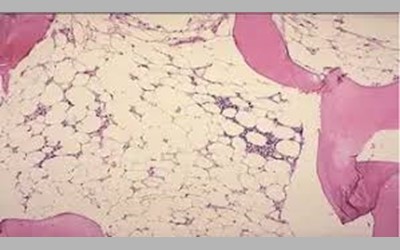

عملکرد اصلی مغز استخوان تولید سلول های خونی جدید است این سلول ها شامل گلبولهای قرمز که اکسیژن را به بافت های مختلف بدن انتقال میدهند ، گلبول های سفید که باعفونت ها مبارزه می کنند و پلاکت ها که برای انقعاد طبیعی خون ضروری هستند، حدود 90 درصد از افراد مبتلا به آنمی فانکونی نارسایی مغز استخوان دارند که منجر به کاهش تمام سلول های خونی می شود.